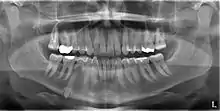

Classifications enable the oral surgeon to determine the difficulty in removal of the impacted tooth. [9] The primary factor determining the difficulty is accessibility, which is determined by adjacent teeth or other structures that impair access or delivery pathway. The majority of classification schemes are based on analysis on a radiograph. The most frequently considered factors are discussed below.

Angulation of tooth

Most commonly used classification system with respect to treatment planning. Depending on the angulation the tooth might be classified as:

This type of classification is based on the amount of impacted tooth that is covered with the mandibular ramus. It is known as the Pell and Gregory classification, classes 1, 2, and 3.[10]

Relationship of tooth to occlusal plane

The depth of the impacted tooth in relation to the adjacent second molar serves as the foundation for this type of classification. This was also given by Pell and Gregory and is known as the Pell and Gregory A, B, and C classification. Relationship to the occlusal plane A-C classes